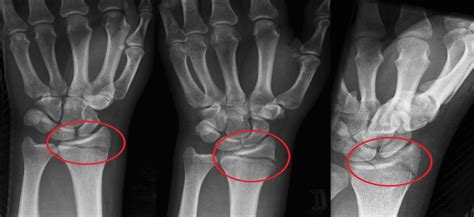

Smith lūžis - tai dilbio stipinkaulio (lot. radius) lūžis, įvykstantis netoli riešo sąnario, kai kaulo distalinė dalis (arčiausiai riešo) lūžta ir pasislenka į delno pusę (voliarinę pusę). Šis lūžis skiriasi nuo dažnesnio Colles lūžio, kai kaulas pasislenka į nugarinę pusę. Smith lūžis dažnai vadinamas „atvirkštiniu Colles lūžiu“ ir sudaro apie 5-10 % visų distalinių stipinkaulio lūžių.

Dažniausi tipai:

• Colles lūžis - (nugarinė) deformacija.

• Smith lūžis - (delno) deformacija.